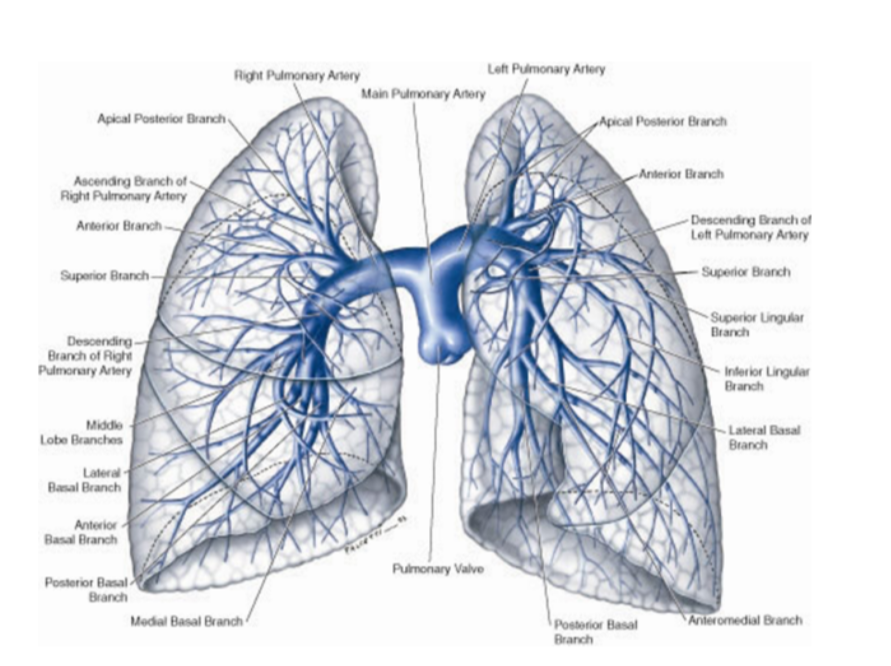

Overall vasculature of the lungs image

Pulmonary arteries (overall)

1 right, 1 left, originate from the pulmonary trunk & carry deoxygenated blood to the lungs from the right ventricle of the heart

Bifurcation of pulmonary trunk occurs to left of midline just inferior to vertebral level TIV/V, and anteroinferiorly to the left of the bifurcation of the trachea

Right vs left pulmonary arteries

Right pulmonary artery —

Slightly longer than left

Crosses horizontally at the mediastinum passes anteriorly & inferiorly to the bifurcation of the trachea, & anteriorly to the right main bronchus — also posteriorly to the ascending aorta, superior vena cava, and upper right pulmonary vein

Enters into root of lung giving off a large branch to the superior lobe of the lung

Main branch continues through hilum to give off a second recurrent branch to superior lobe before dividing to supply both the midline & inferior lobes

Left pulmonary artery —

Shorter than the right, anterior to the descending aorta & posterior to the superior pulmonary vein

Pulmonary veins —

On both sides — superior & inferior pulmonary vein

Carry oxygenated blood from lungs back to heart

Begin at hilum, pass through root of lung, & immediately drain into left atrium

Bronchial arteries

Along. with the veins form part of the nutritive system of vasculature of the lungs

Interconnect within the lung with branches of the pulmonary arteries & veins

Originate from the thoracic aorta or one of its branches —

A singular right bronchial artery normally arises from the third posterior intercostal artery

Occasionally originates from upper left bronchial artery

2 left bronchial arteries directly arise from the anterior surface of the thoracic aorta —

Superior left bronchial artery arises — vertebral level TV

Inferior left bronchial artery arises inferior to left bronchus

They run on the posterior surfaces of the bronchi & ramify in the lungs to supply pulmonary tissues